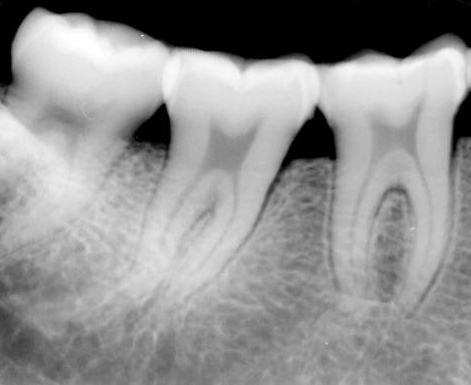

Дентальный (или прицельный) снимок

Имплантация, протезирование, синус-лифтинг, лечение каналов зуба — все эти операции невозможны без рентгена. Сделать снимок зубов необходимо, чтобы оценить состояние костной ткани, проверить заполнение каналов (снимок корней зубов), выявить развитие скрытого кариеса, который может появляться под пломбой, коронкой или в межзубных промежутках. Рентген зуба показывает также состояние периодонта (ткани вокруг корня зуба) и пародонта (ткани вокруг всего зуба), трещины или воспаление каналов. С помощью рентгена Врач стоматолог может поставить точный диагноз, особенно если жалобы Пациента и симптомы позволяют предположить несколько болезней.

Делается на визиографе.